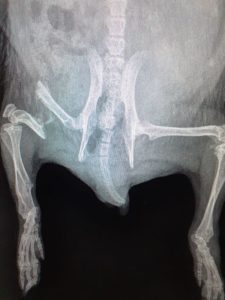

Two hogs have been to the vets this morning with broken hind legs, our vet is going to try and pin them both tomorrow. The first image is a clean